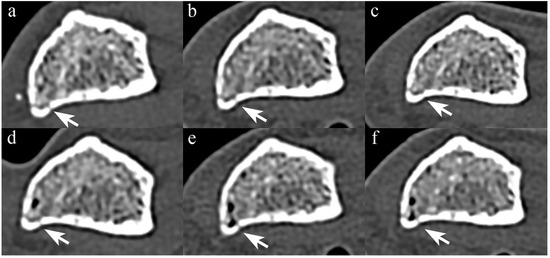

Comparison of STD images (Figure 1) revealed no significant difference in the subjective scores of cortical bone visibility between PCCT and EIDCT (Table 4).

Figure 1. Comparison of photon-counting CT (PCCT) and energy-integrating-detector CT (EIDCT) images in the standard (STD) mode. Images were obtained using (a) Alpha, (b) Drive, (c) X.cite, (d) Force, (e) AS, and (f) Flash scanners. Qualitative scores were made using the image (b) as a reference. Although the appearance of cortical bone and trabecular bone in each image is similar, the PCCT image (a) has less noise than the EIDCT images (bf).

Even in UHR mode, there was no significant difference in the score for the visibility of trabecular bone between PCCT and all EIDCTs, and there was also no significant difference in the visibility of cortical bone with three EIDCTs (Figure 2 and Table 5). In contrast, PCCT had significantly higher scores of image quality than three EIDCTs in STD mode and all EIDCTs in UHR mode.

Figure 2. Comparison of PCCT and EIDCT images in ultra-high-resolution (UHR) mode. Images were obtained using (a) Alpha, (b) Drive, (c) X.cite, (d) Force, (e) AS, and (f) Flash scanners. Qualitative scores for all images were obtained by using the image in Figure 1b as a reference. Although the appearance of cortical bone and trabecular bone in each image is similar, the PCCT image (a) has significantly less noise than the EIDCT images (bf).